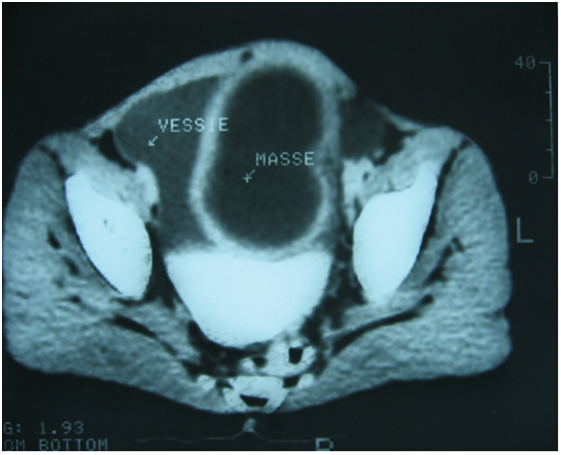

The abdominal ultrasound requested in first intention had mounted a cystic mass, pushing laterally the bladder and could correspond either to a diverticulum of the bladder, or to a cyst of the ovary (Figure 1). CT scan was also performed and had objectified a cystic mass under the umbilical, median compressing behind the bladder dome with overflow to the right of the bladder horn, evoking a cyst of the urachus or an ovarian cyst (Figure 2). Surgical exploration revealed a cystic mass forming part of the bladder dome, evoking a cystic tumor of the urachus. The mass was removed by removing the implantation base from the bladder dome. The postoperative consequences were simple. The pathological report concluded that there was a hydatid cyst of the bladder dome.

Figure 1 Ultrasound image showing a cystic mass pushing back the bladder laterally.